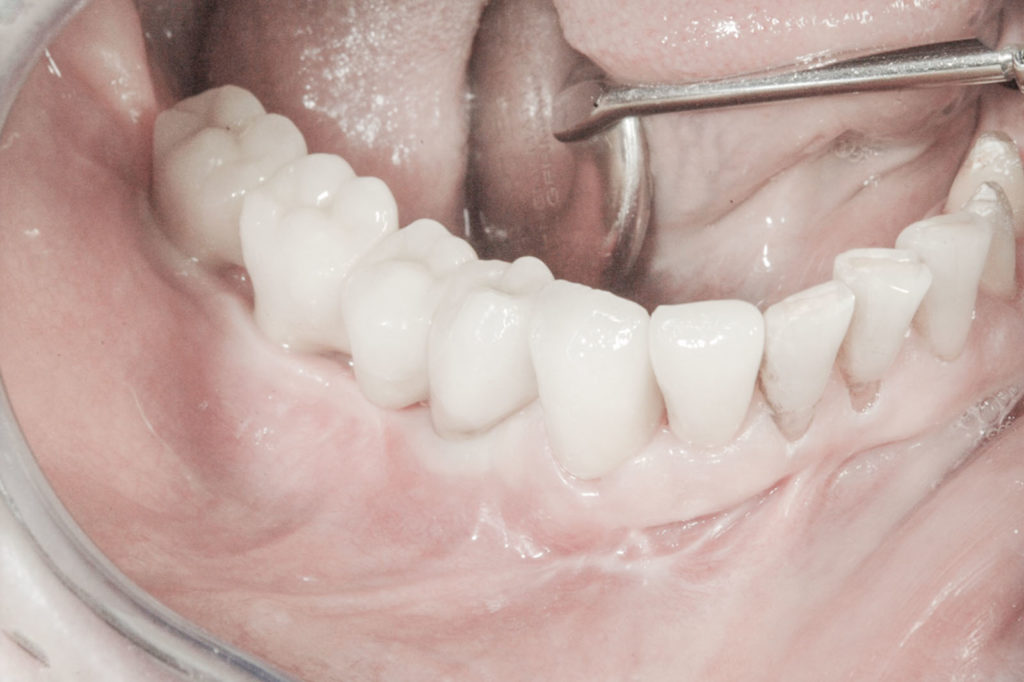

Procedury te są stosowane w sytuacji niedostatecznej ilości kości, skutkującej odsłonięciem gwintu, podczas gdy wszczepiamy implanty stomatologiczne lub też jako zabiegi poprzedzające ich wprowadzenie.​